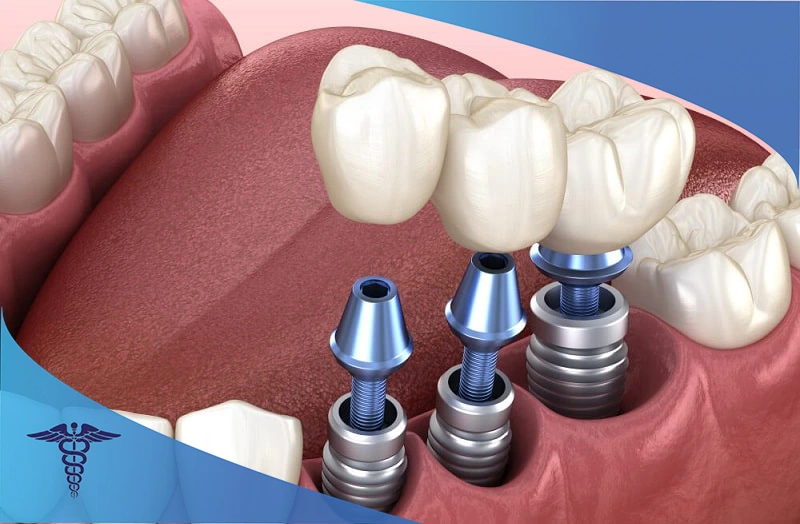

ایمپلنت دندانی

اگر یک یا چند دندان خود را از دست داده اید، ایمپلنت دندان می تواند یک گزینه عالی برای اصلاح لبخند شما باشد. ایمپلنت های دندانی جایگزین دندان های از دست رفته می شوند و به شما کمک می کنند استخوان فک خود را در ناحیه آسیب دیده حفظ کنید. آن ها با ترکیب یک روکش و پیچ تیتانیومی در داخل فک شما قرار می گیرند و تا چندین سال مانند یک دندان طبیعی برای شما کار می کنند.